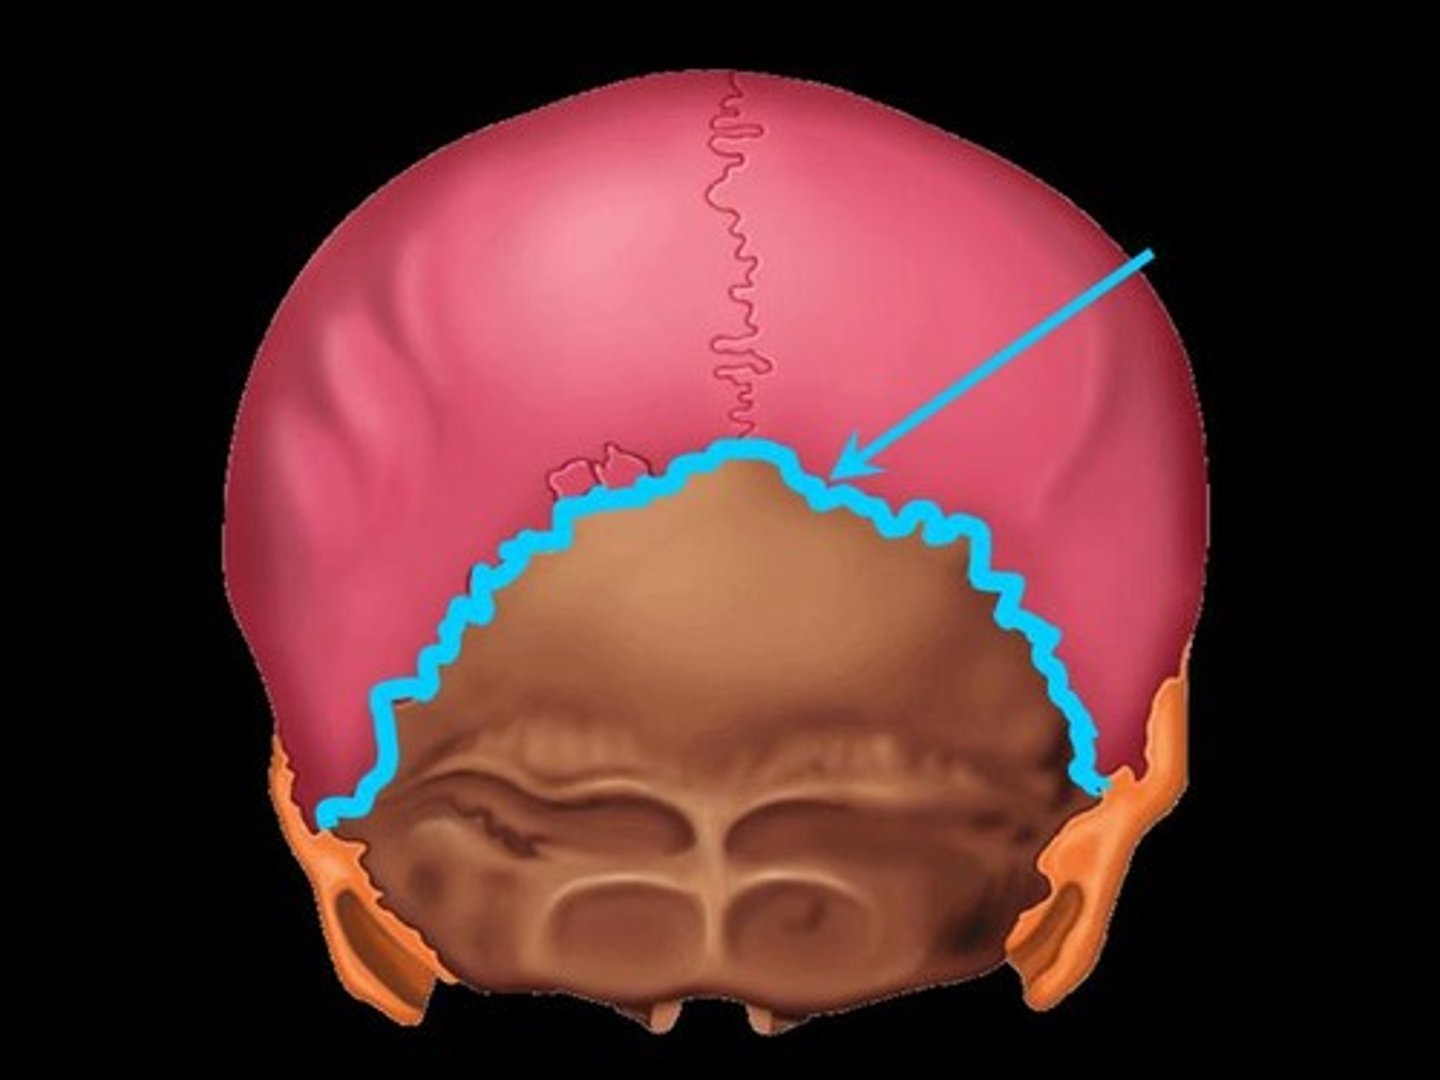

lambdoid suture

between parietal bones and occipital bone

lambda

junction of sagittal and lambdoidal sutures

premature closure of sagittal suture resulting in posterior elongation

lambdoid craniosynostosis

closing of one side of the lambdoid suture resulting in posterior bulging at the contralateral side